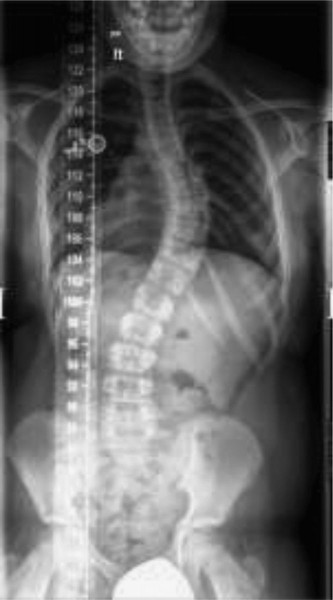

CASE 12 You are in your scoliosis clinic today and your patients are already in…